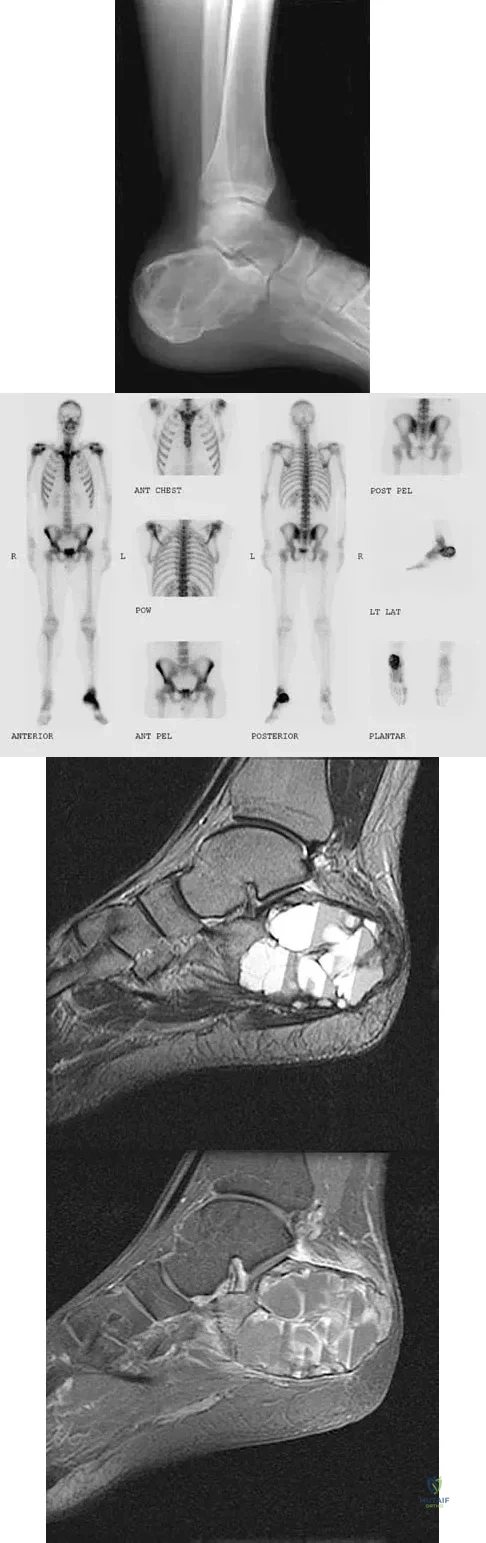

A 23-year-old man has had heel pain and fullness for the past several months. He reports that initially the pain was present only with activity, but more recently the pain has become constant. Figures 53a through 53d show a radiograph, a bone scan, and T2-weighted and gadolinium MRI scans. What is the most likely diagnosis?

Explanation